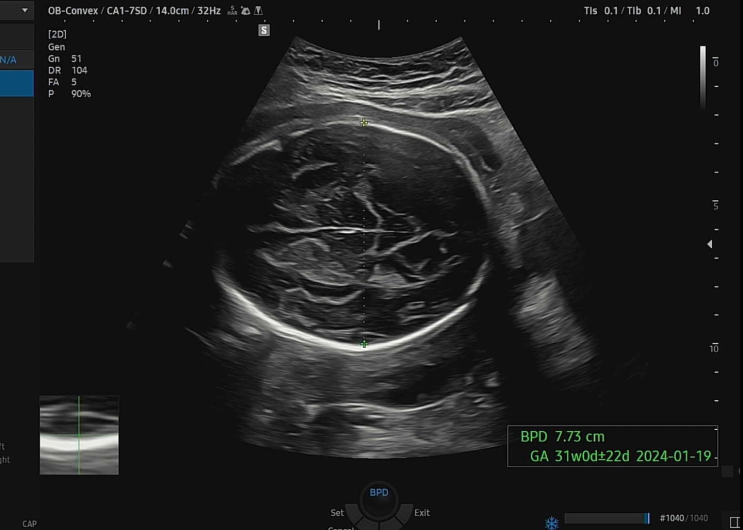

[임신일기]임신32주 - 출산일 확정 (제왕절개)

30주 이후로 2주마다 산부인과 검진이 예약되어있다. 4주마다 가던게 2주로 줄어드니 얼마전에 봤는데 금방...

[임신일기]임신30주 - 한 달 만에 본 아기

30주차! 드디어 막달에 접어들었다. 출산까지 약 2달여 남짓 남았다. 배도 꽤나 불렀고, 조금 빠르게 걷는...